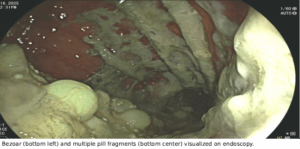

Duheric-Imagev2-642×336